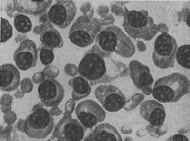

Патоморфологическим субстратом мієломної хвороби є ретикулярні плазматичні клітини кісткового мозку, лімфатичних вузлів, селезінки, печінки та ін. На гістологічних зрізах мієломних вузлів, як і в препаратах кісткового мозку, отриманих шляхом пункцій або трепанобиопсии кісток, виявляються характерні «миеломные клітини» - своєрідні, зазвичай великі плазматичні і ретикулярні клітини. Різноманіття морфологічних картин, властивих М. б., обумовлено різними стадіями розвитку і різним ступенем малігнізації (злоякісної трансформації) ретикулярних плазматичних клітин (рис. 1-6).

![]() Рис. 1. Стернальный пунктат при мієломної хвороби: плазмомиеломная метаплазія  |